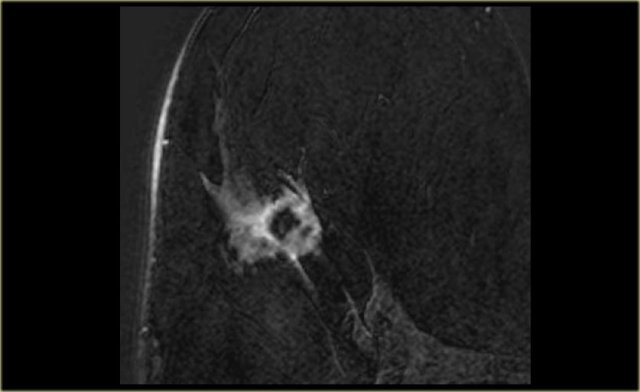

Margin

Margins can be described as smooth, irregular, or spiculated .

Spiculated margins are frequently a feature of malignant breast lesions and radial

scars.

If a mass has spiculated margins, it has an 80% chance of being malignant.

The image on the far left shows a spiculated mass, i.e. 80% chance of being malignant. .

Next to it the corresponding gross pathologic specimen.

You can see the spiculations invading the surrounding tissue in both.

Just like on mammography, this lesion is has a high likelihood of malignancy and would be labelled BIRADS 5.